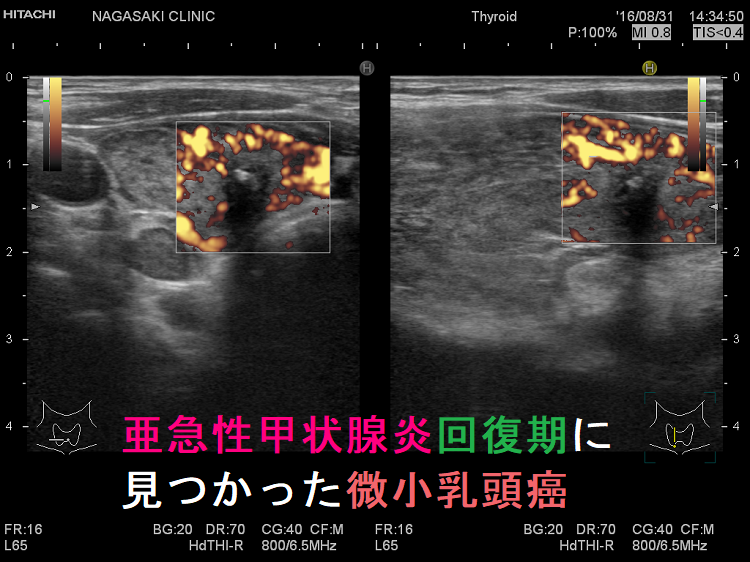

亜急性甲状腺炎に甲状腺乳頭癌が合併

ステロイド治療の後、甲状腺全体の腫れが引くと、甲状腺乳頭癌の低エコー域も縮小するので、亜急性甲状腺炎の炎症と勘違いする可能性があります。例え縮小しても、消えなければ、しかも石灰化を伴っていれば甲状腺乳頭癌を疑うべきです。亜急性甲状腺炎が沈静化しない内に穿刺細胞診すると、炎症所見が混ざって、病理医が甲状腺乳頭癌の診断を下し難い様です。